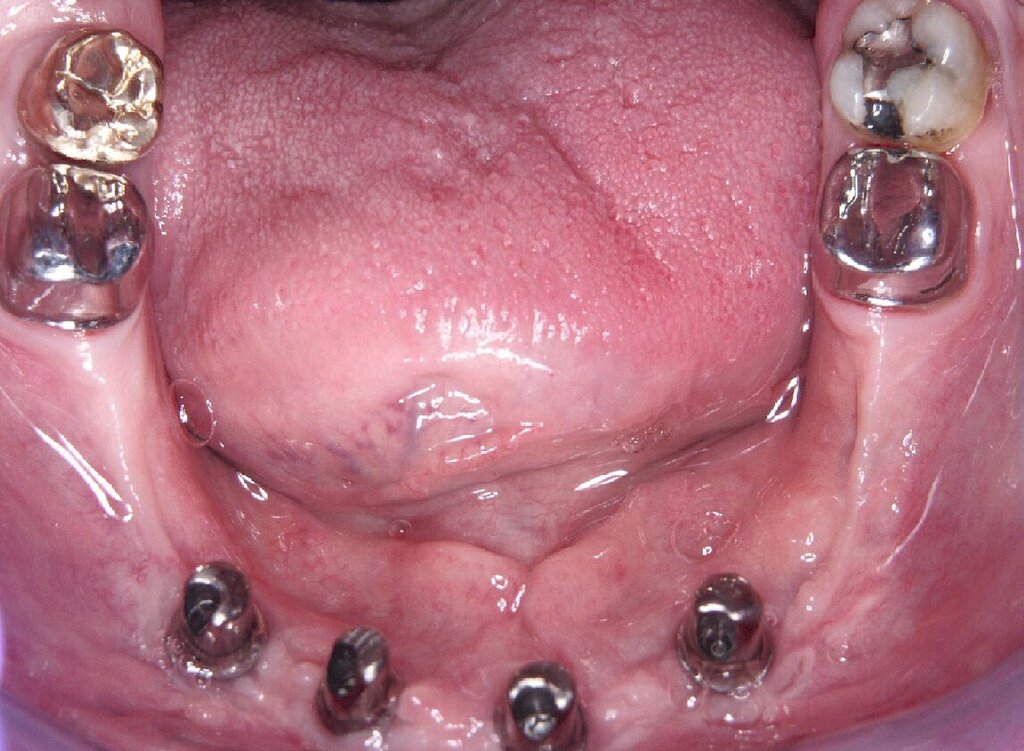

Eine präoperativ vorbereitete Interimsprothese, die über zwei gegossene Bonwill-Klammern sowie das verbliebene Implantat in regio 35 stabil abgestützt war, diente gleichzeitig als Verbandsplatte (Abb. 1f). Auf eine Glättung scharfer Knochenkanten oder die Nivellierung der Kieferkämme wurde verzichtet, um einen iatrogenen Knochenverlust zu vermeiden und das regenerative Potenzial des verbliebenen Knochens zu nutzen (Abb. 1g). Bereits bei der röntgenologischen Kontrolle nach drei Monaten war eine deutliche Zunahme des Knochens im Bereich der alten Implantatpositionen zu erkennen (Abb. 1h). Eine Nachimplantation von vier Implantaten in den Positionen 32, 34, 42 und 44 erfolgte neun Monate nach der Explantation und einer vorangegangenen Verbesserung der Weichgewebsbedeckung durch multiple freie Schleimhautransplantate vom harten Gaumen. Die knöcherne Regeneration unter der gut abgestützten Modellgussprothese verlief so günstig, dass sich der vertikale Höhenverlust des Alveolarkamms im Bereich der gescheiterten Implantate auf circa 2 mm begrenzen ließ. Das zur Entlastung der Kieferkämme und der einheilenden Implantate außerordentlich hilfreiche Implantat in regio 35 wurde erst nach dem Einheilen der nachgesetzten Implantate entfernt. Nach der Einheilzeit der Implantate von weiteren drei Monaten wurde eine kombiniert Zahn/Implantat-gestützte Teleskopprothese mit intraoral verklebten Galvano-Sekundärkronen eingegliedert (Abb. 1k bis 1m). Inzwischen ist diese, wie eine herausnehmbare Brücke abgestützte UK-Prothese seit zehn Jahren funktionstüchtig ohne Zeichen einer Periimplantitis an den vier Implantaten.